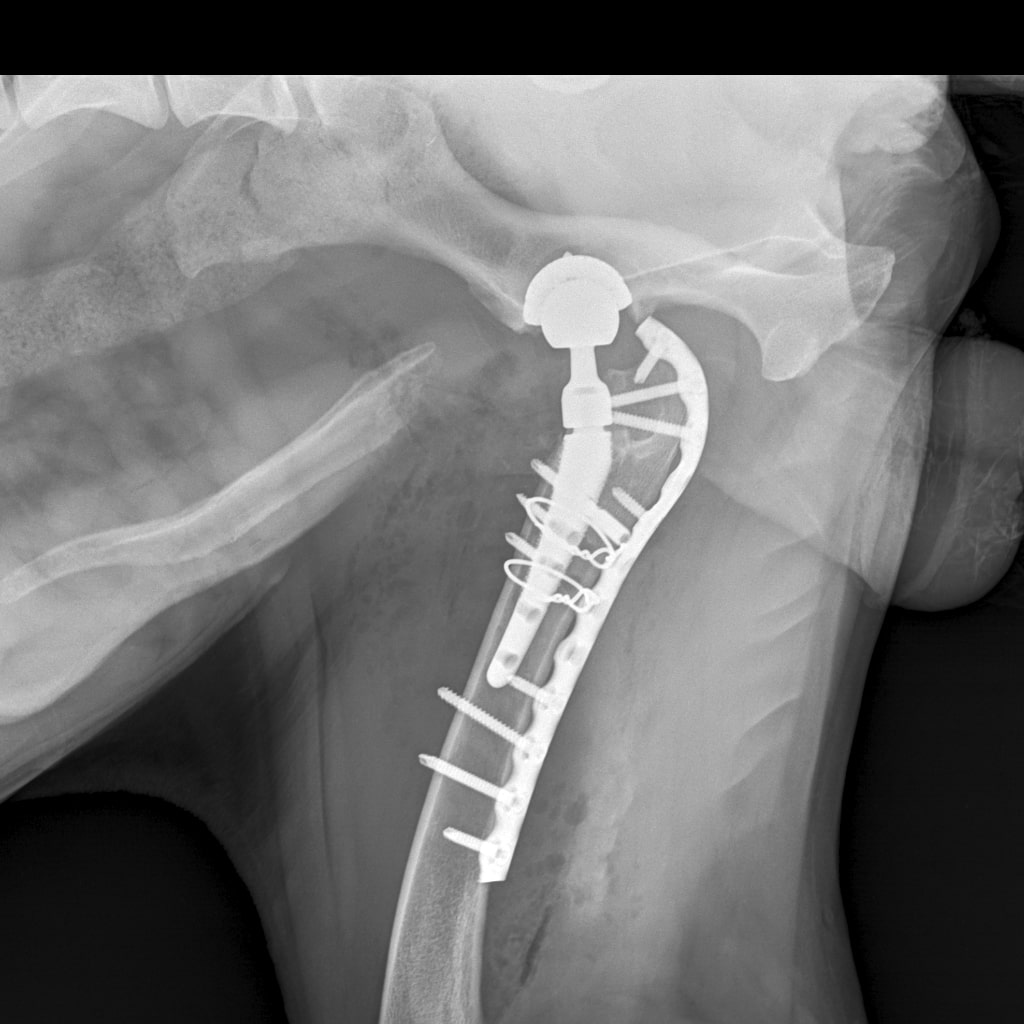

8A836050-66CA-42B2-94D3-F13B288A592B.jpeg

39B2671E-39B9-4502-9E11-ADB169612F24.jpeg

6950B9C9-79EA-4F34-A780-9C3C6BA31B49.jpeg

58C20B18-AA4E-4386-BF83-56CE5E282844.jpeg

Наш металлический мальчик

Железный дровосек